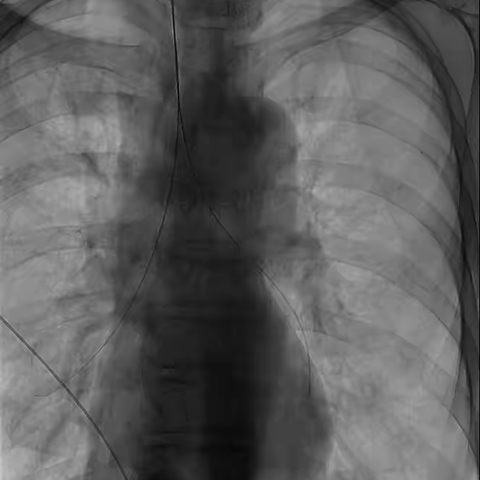

主动脉弓旁小细胞肺癌粒子植入术后纵隔血肿